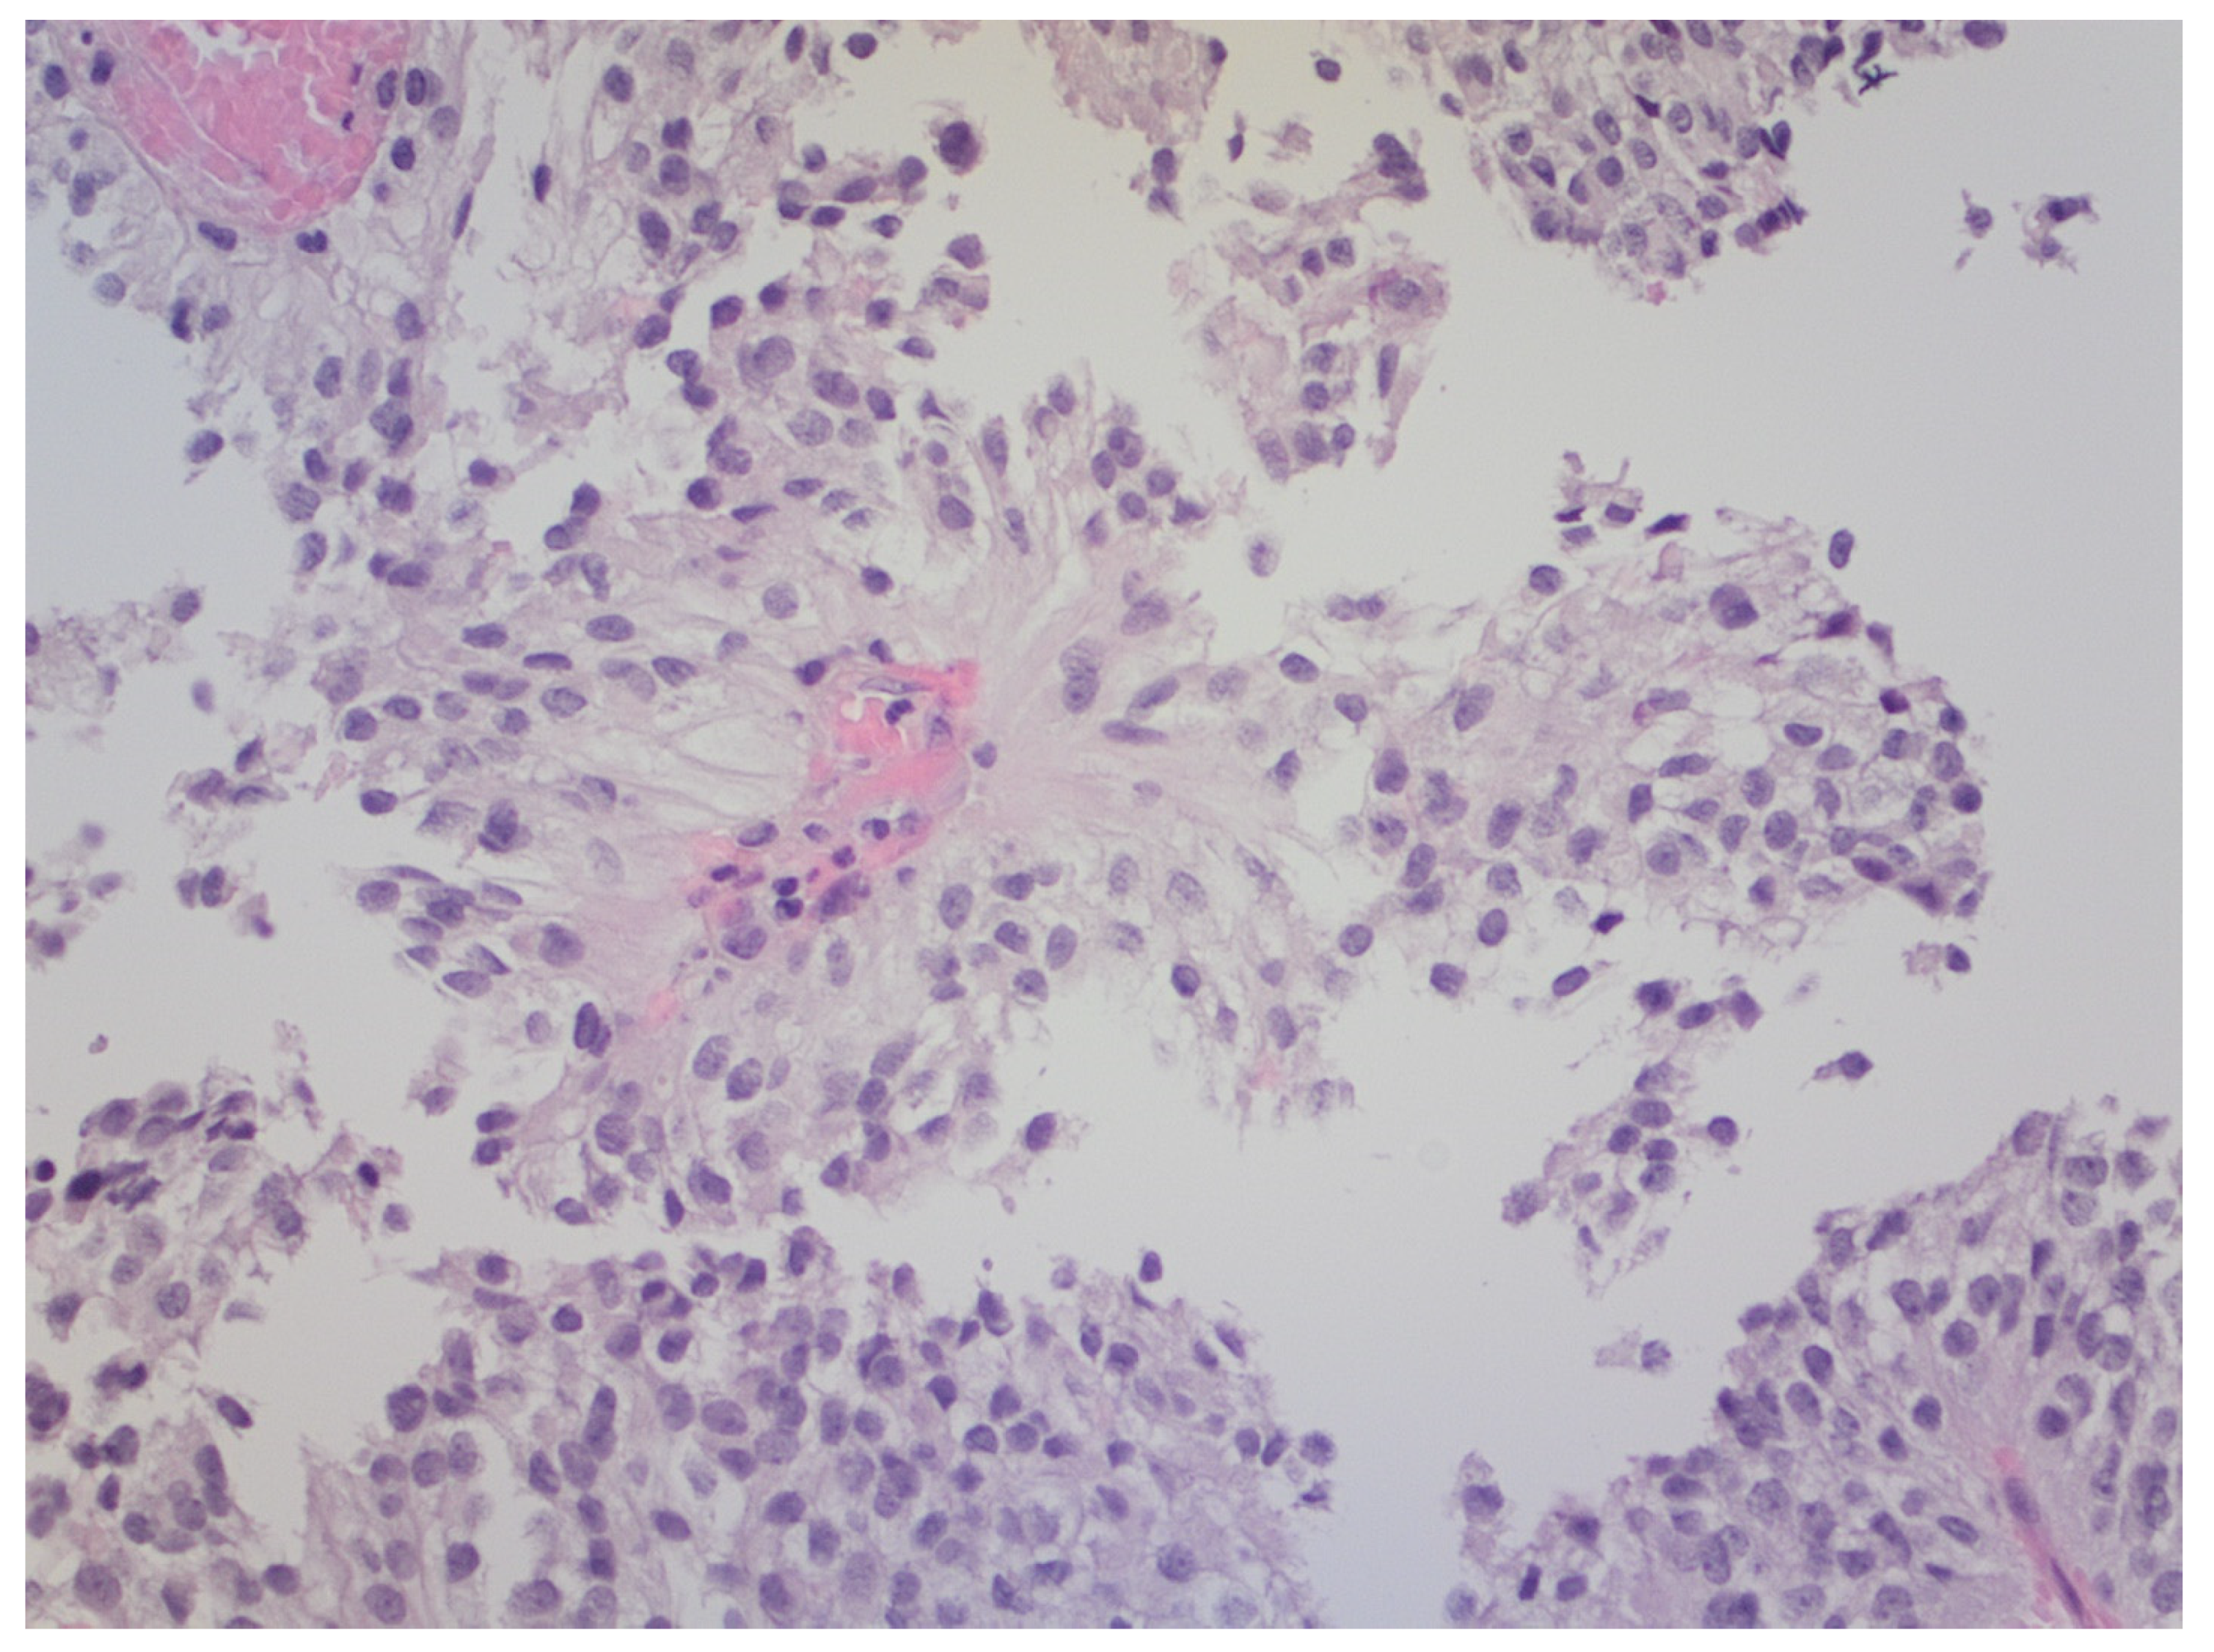

2.1. Case 1

2.2. Case 2